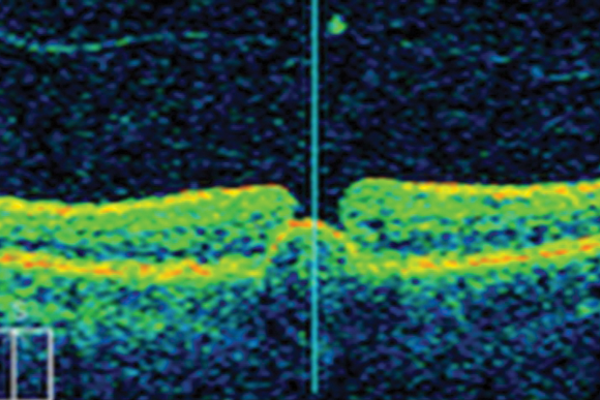

Vitreomacular traction and full thickness macular hole